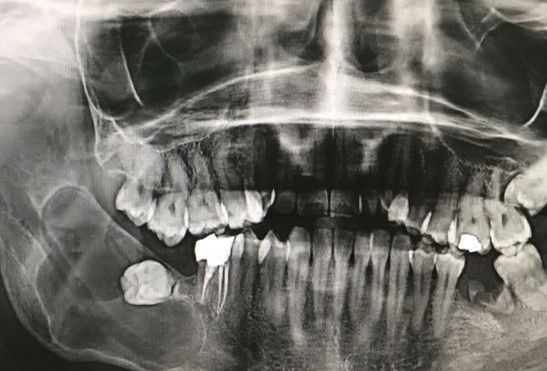

Terceros molares o muelas del juicio

Durante la salida de estas piezas dentales, por falta de espacio, muchas veces no se logra su erupción completa debido a una enquistación, lo cual puede generar dolores o molestias en el paciente.

Para evitar infecciones, quistes foliculares o diversos dolores en el paciente, se sugiere la extirpación de las muelas del juicio.